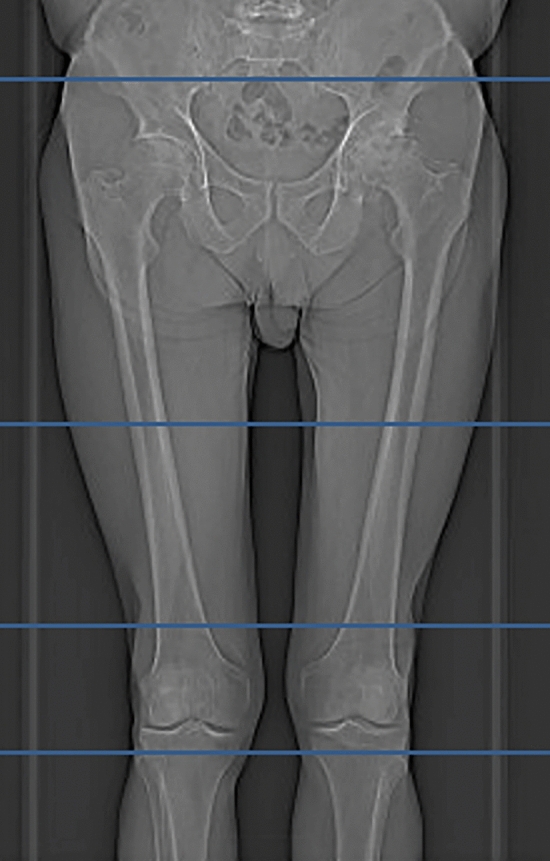

In addition to our standard radiographic work-up (pelvic ap view and unilateral cross-table lateral view), a tin-filtered ultra-low-dose CT (protocol Sn 140 kV/150 mAs) was performed on a 128-slice-CT scanner (SOMATOM Edge Plus, Siemens Healthineers). The scan region included the hip joint (3 cm above the acetabular roof) and the 1st half of the femur (11 cm below the lesser trochanter). An additional short scan of the distal femoral condyle was obtained for femoral torsion measurement as this is of clinical interest (Fig. 2).

Fig. 2.

Image depicting the scout of the CT scan protocol. The scanned regions are bordered by the blue boxes and include the hip joint the proximal femur and the distal femoral condyle